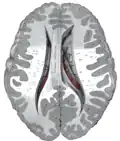

Structure

Along with the putamen, the caudate forms the dorsal striatum, which is considered a single functional structure; anatomically, it is separated by a large white-matter tract, the internal capsule, so it is sometimes also described as two structures—the medial dorsal striatum (the caudate) and the lateral dorsal striatum (the putamen). In this vein, the two are functionally distinct not because of structural differences, but merely because of the topographical distribution of function.

The caudate nuclei are near the center of the brain, sitting astride the thalamus. There is a caudate nucleus in each hemisphere of the brain. Each nucleus is C-shaped, with a wider "head" (caput in Latin) at the front, tapering to a "body" (corpus) and a "tail" (cauda). Sometimes a part of the caudate nucleus is called the "knee" (genu).[6] The caudate head receives its blood supply from the lenticulostriate artery; the tail of the caudate receives its blood supply from the anterior choroidal artery.[7]